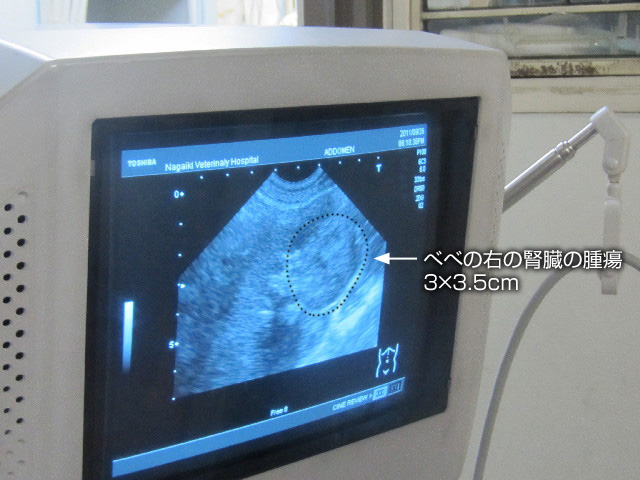

....そうしたら、思いもよらないものがみつかりました(--〆)

右の腎臓に3×3.5cmもある腫瘍が。

3×3.5cmというと、腎臓の25%を占める大きさでかなり大きいらしいです。

↓画像の黒い破線の少し内側が腫瘍。

ちなみに左の腎臓に腫瘍はありませんでした。

先生の指先のあたりの、胃の形のような物が腫瘍です。